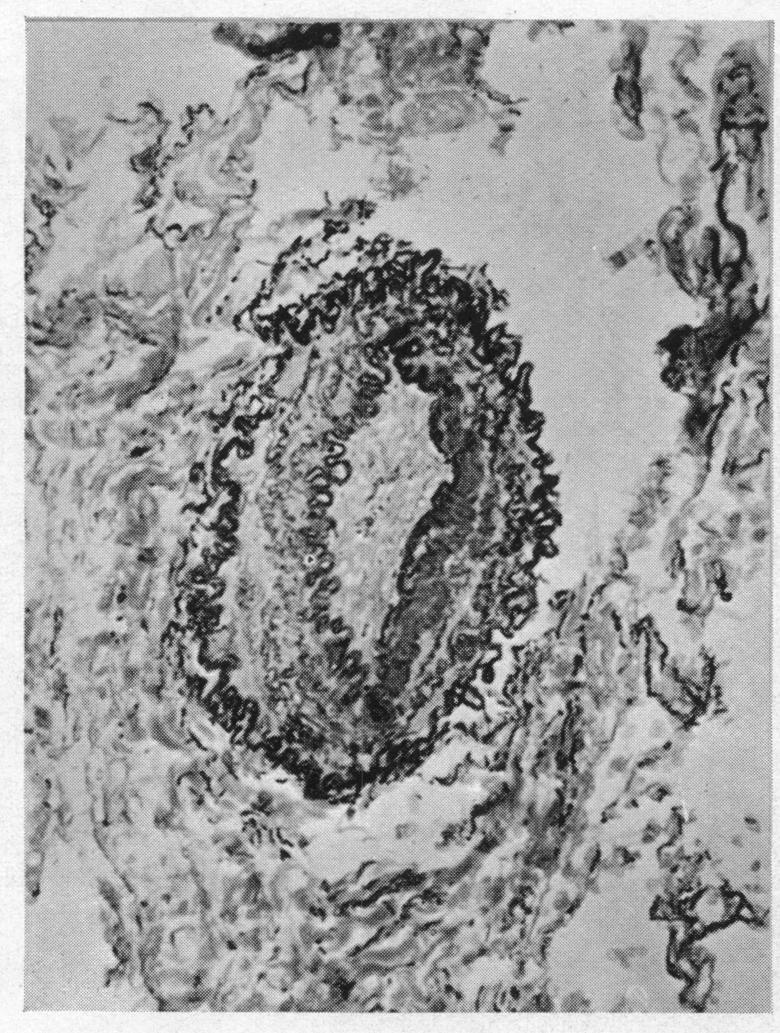

Eisenmenger's complex.

Br Heart J. 1955 Jul;17(3):273-84. doi: 10.1136/hrt.17.3.273.

Pulmonary vascular changes in Eisenmenger's complex.

J Pathol Bacteriol. 1959 Jan;77(1):141-7. doi: 10.1002/path.1700770115.